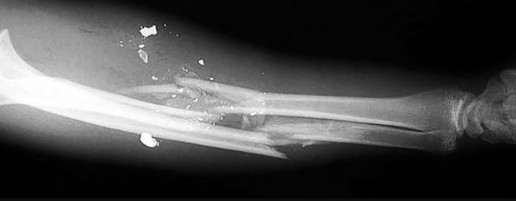

Question 21

A 12-year-old obese boy presents with left hip pain and an obligate external rotation of the hip during flexion. A radiograph is shown below. What is the most appropriate initial management for the condition demonstrated?

Explanation

The clinical presentation and radiograph represent a stable Slipped Capital Femoral Epiphysis (SCFE). The gold standard for initial management of a stable SCFE is in-situ pinning, typically utilizing a single partially threaded cannulated screw placed in the center-center position of the epiphysis to prevent further slip and promote physeal closure.